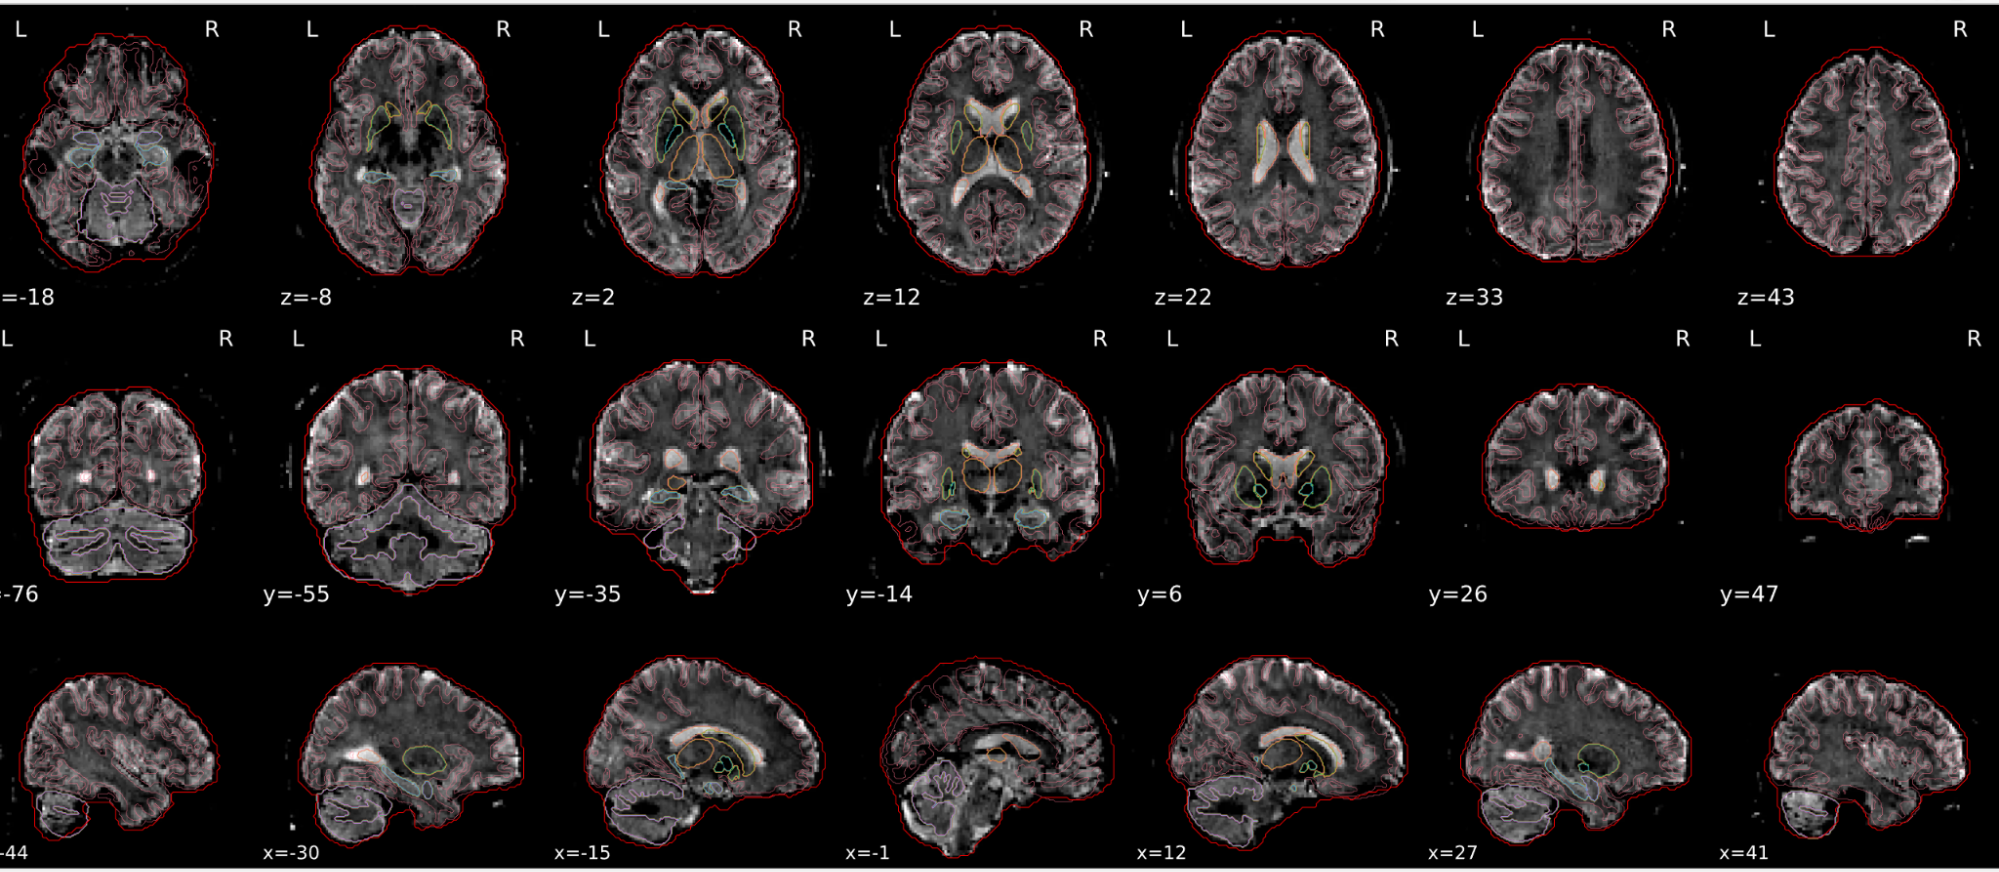

dT1w spatial normalisation

This QC step shows the registration of the T1 image to MNI space.

The registered T1 image is shown in the background with a brain atlas in MNI space as an overlay.

Example of a good subject

- If the registration performed well, you should see an overlap (i.e., correspondence of structures) between the MNI template and the T1 registered to the MNI space.

Example of a bad subject

- In case of poor registration, you should see a misalignment between the MNI template and the T1 (e.g., brain shifted down).

Summary

| good | bad |

|---|---|

| Structures of the MNI template and the registered T1 are well aligned | Structures of the MNI template and the registered T1 aren’t well aligned, e.g. brain is shifted downwards |